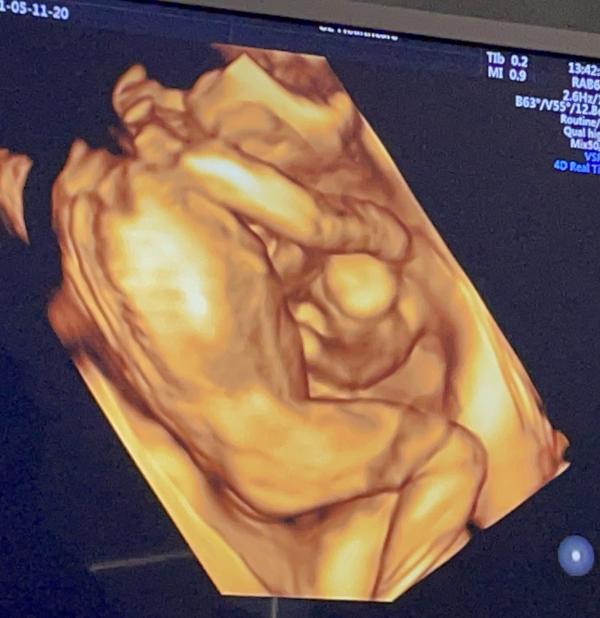

Нашла фото с узи и удивилась как удачно Боренштейн кадр поймала) к слову это был первый и последний раз, когда Сара показала личико)) всегда за брата пряталась👀 Галентовский на втором скрининге поймал только попу😅

Первое фото 28, второе где то 18-20